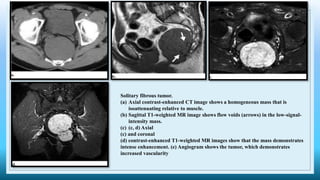

Solitary fibrous tumor.

(a) Axial contrast-enhanced CT image shows a homogeneous mass that is

isoattenuating relative to muscle.

(b) Sagittal T1-weighted MR image shows flow voids (arrows) in the low-signal-

intensity mass.

(c) (c, d) Axial

(c) and coronal

(d) contrast-enhanced T1-weighted MR images show that the mass demonstrates

intense enhancement. (e) Angiogram shows the tumor, which demonstrates

increased vascularity

 CT - well-circumscribed mass with soft-tissue attenuation that typically demonstrates intense

contrast enhancement

Areas of hemorrhage, necrosis, and cystic change may be seen.

 MRI - low to intermediate signal intensity on T1- and T2- weighted MR images a result of

fibrous tissue, but areas of myxoid or cystic degeneration may demonstrate high signal intensity

on T2-weighted images.

Hypervascularity with prominent enhancement and flow voids is common.